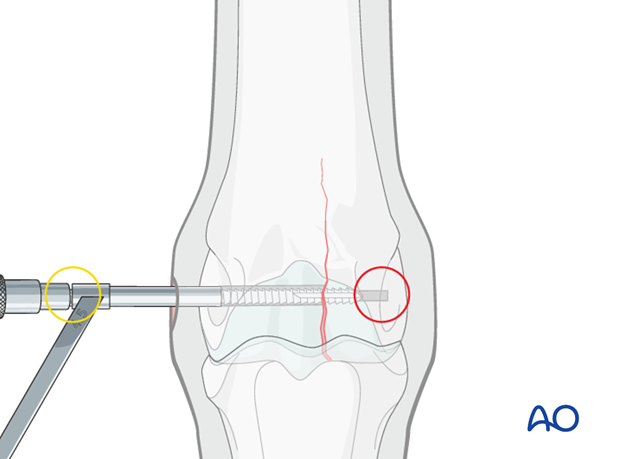

The 4.5 mm drill guide is subsequently placed over the 2.5 mm pin (A). The pin is removed (B) ...

... and the 4.5 mm tap inserted through the guide (C).

The hole is tapped routinely, keeping the very dense bone in mind. It is critical to tap completely through the far cortex (red circle). The bone is so dense that even a single millimeter of untapped bone may prevent complete insertion and tightening of the screw.

A long tap is strongly preferred to avoid impinging the end of the drill on the edge of the drill guide (yellow circle). This could result in stripping the threads in the hole or breaking the tap.